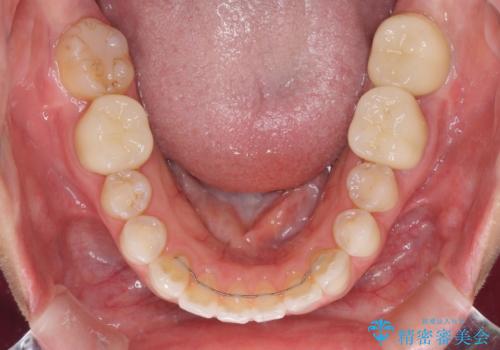

矯正治療後は、奥歯の虫歯や銀歯を補綴・修復治療することとしました。

上顎歯列を下顎に対して4mmほど移動させる必要があったため、治療は長期化することが予想されましたが、患者様にはこちらの期待以上にゴムかけなどに協力いただき、補綴治療も含めて2年強で終えることができました。